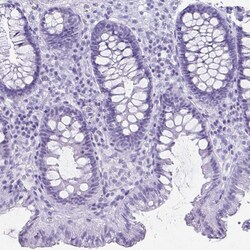

Invitrogen™ ATP4B Polyclonal Antibody

Immunogen sequence: TPDYQDQLRS PGVTLRPDVY GEKGLEIVYN VSDNRTWADL TQTLHAFLAG YSPAAQEDSI NCTSEQYFFQ ESFRAPNHTK FSCKFTADML Highest antigen sequence indentity to the following orthologs: Mouse - 83%, Rat - 80%.

| Immunohistochemistry (Paraffin) | |